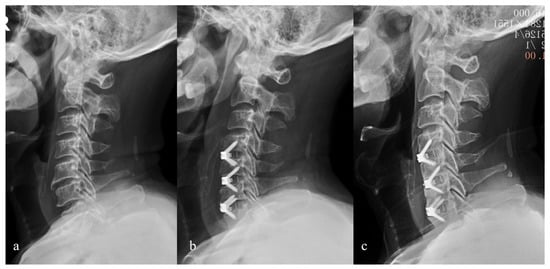

2. Materials and Methods

3. Results